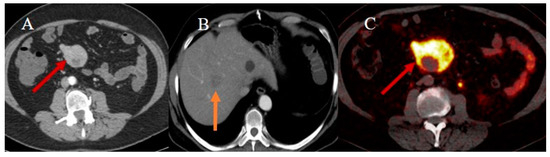

- Jayaprakasam, V.S.; Paroder, V.; Schöder, H. Variants and pitfalls in PET/CT imaging of gastrointestinal cancers. Semin. Nucl. Med. 2021, 51, 485–501. [Google Scholar] [CrossRef] [PubMed]

- Koppula, B.R.; Fine, G.C.; Salem, A.E.; Covington, M.F.; Wiggins, R.H.; Hoffman, J.M.; Morton, K.A. PET-CT in clinical adult oncology: III. Gastrointestinal malignancies. Cancers 2022, 14, 2668. [Google Scholar] [CrossRef] [PubMed]

- Scott, A.T.; Howe, J.R. Management of small bowel neuroendocrine tumors. J. Oncol. Pract. 2018, 14, 471–482. [Google Scholar] [CrossRef] [PubMed]

- Kandathil, A.; Subramaniam, R.M. Gastroenteropancreatic neuroendocrine tumor diagnosis: DOTATATE PET/CT. PET Clin. 2023, 18, 189–200. [Google Scholar] [CrossRef]

- Shell, J.; Keutgen, X.M.; Millo, C.; Nilubol, N.; Patel, D.; Sadowski, S.; Boufraqech, M.; Yang, L.; Merkel, R.; Atallah, C.; et al. 68-Gallium DOTATATE scanning in symptomatic patients with negative anatomic imaging but suspected neuroendocrine tumor. Int. J. Endocr. Oncol. 2018, 5, IJE04. [Google Scholar] [CrossRef]

- Bonomi, A.; Romario, U.F.; Funicelli, L.; Conti, G.; Luc, M.R.; Ceci, F.; Pozzi, S.; Radice, D.; Fazio, N.; Bertani, E. Diagnosis and staging of small intestinal neuroendocrine tumors with CT enterography and PET with Gallium-68: Preoperative risk stratification protocol. Langenbecks Arch. Surg. 2024, 409, 63. [Google Scholar] [CrossRef]